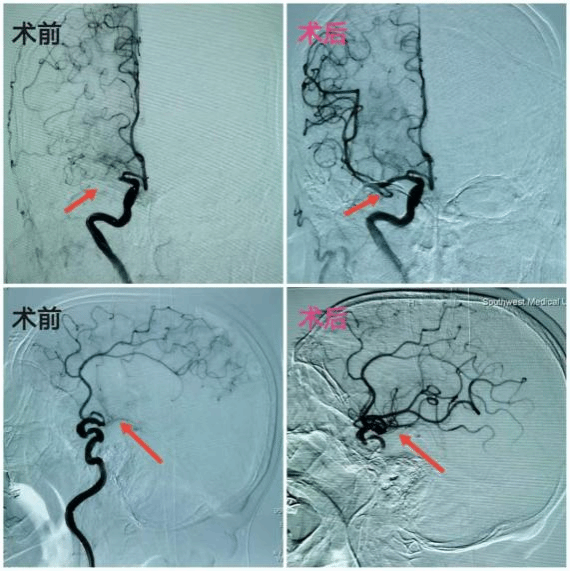

4.颅内动脉瘤

颅内动脉瘤是导致蛛网膜下腔出血的主要因素之一。脑动脉瘤的产生,是由于脑动脉壁先天性缺陷和血管腔内压力增高,在血流不断冲击的情况下,血管壁出现了气球状的隆起,因形似肿瘤,被称为动脉瘤。经股动脉穿刺,采取动脉瘤弹簧圈栓塞术、血流导向密网支架植入术,具有手术创伤小,手术时间短,并发症少,术后恢复快,动脉瘤复发率低等特点。